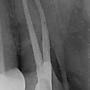

4F推: 建議給根管專科醫師尋求第二意見哦06/28 16:25